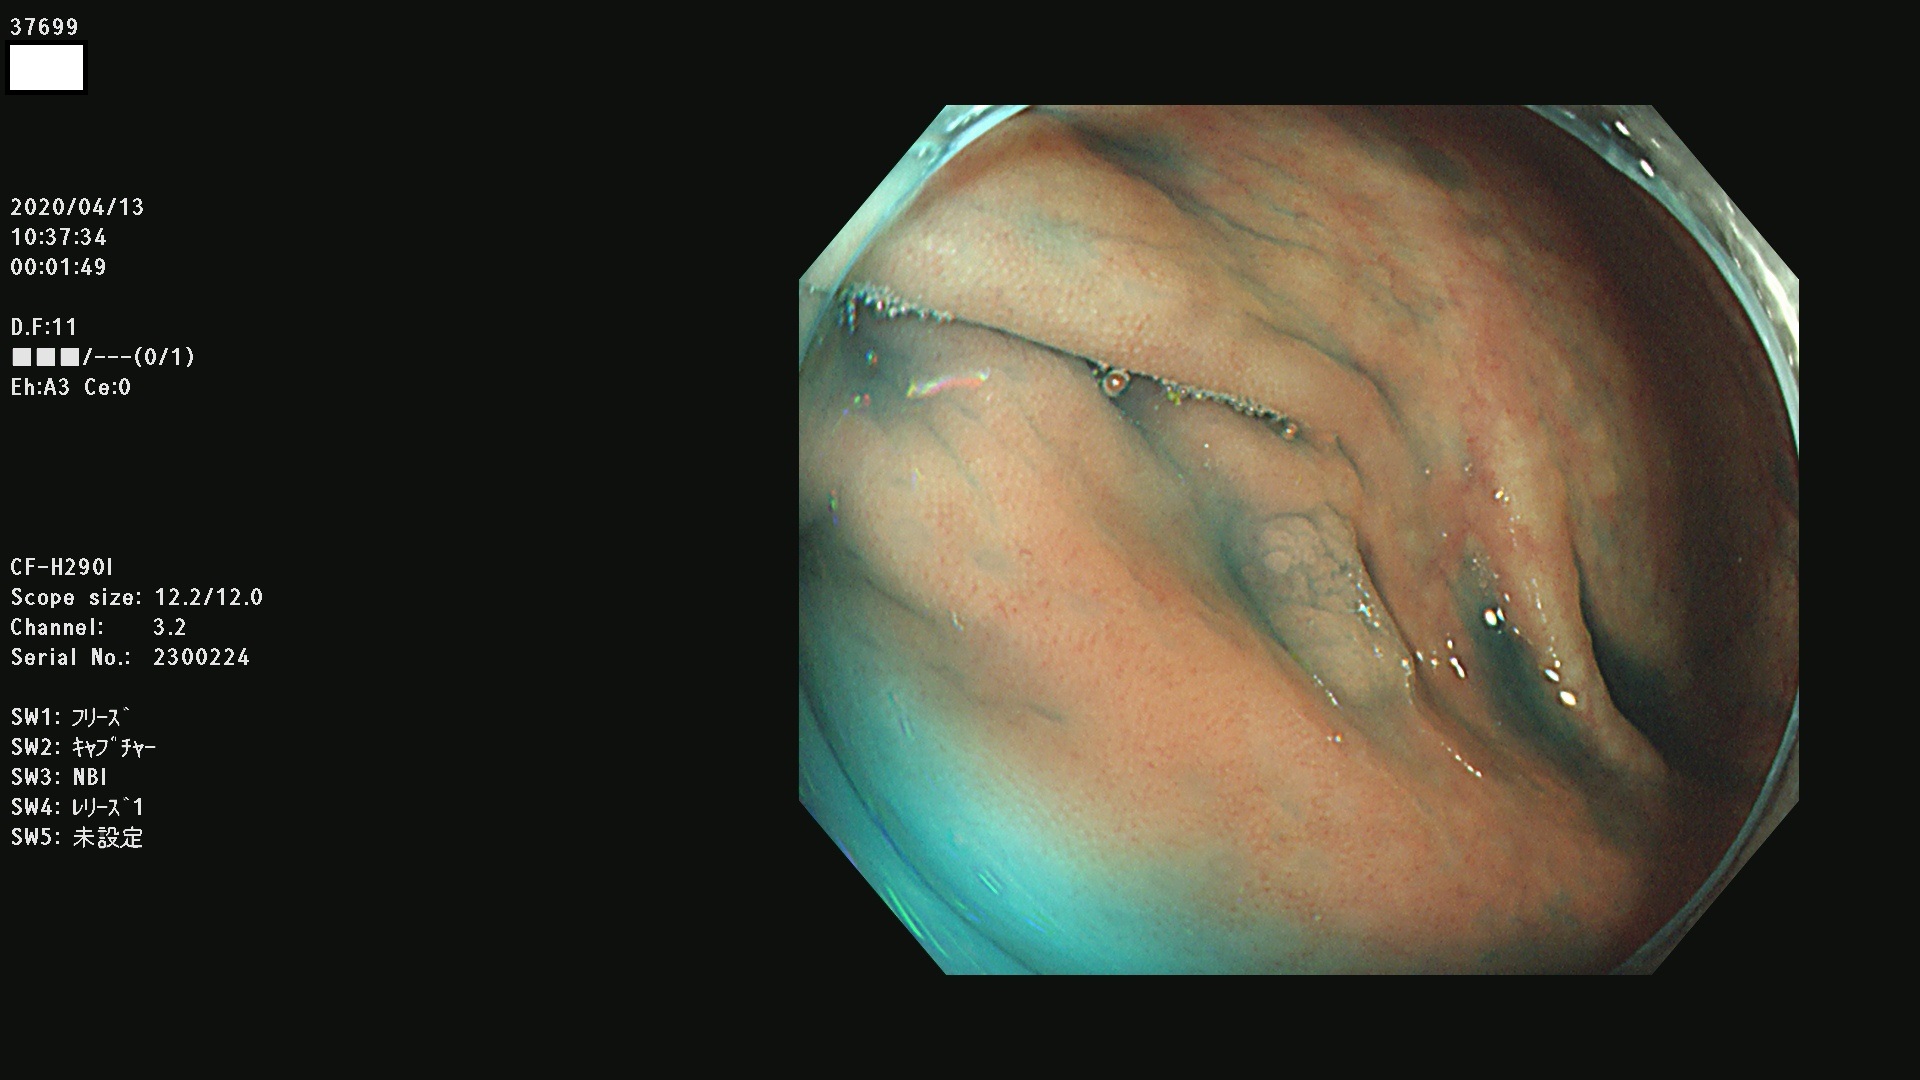

37600 37601 37602 37603 37604 37605 37606 37607 37608 37612 37614 37616 37618 37619 37620 37621 37622(SSAPのみ) 37623(SSAPのみ) 37624 37626 37627 37628 37629 37632 37633 37635 37636(SSAPのみ) 37639 37640 37641 37642 37643 37644 37647(SSAPのみ) 37648 37649 37650 37652 37653 37655 37657 37659 37660 37662 37664 37666 37668(SSAPのみ) 37670 37671 37672 37676 37677 37678 37679 37680 37682 37684 37685(SSAPのみ) 37686 37687 37688 37689 37690 37691 37692(SSAPのみ) 37693 37694 37695 37696 37697 37699

発見困難で危険性の高い平坦型病変(上記100名より抽出)